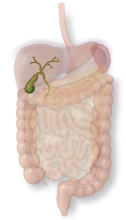

The gallbladder concentrates and stores bile as a pear-shaped sac which it can release to help digestion after a fatty meal.

The gallbladder concentrates and stores bile as a pear-shaped sac which it can release to help digestion after a fatty meal.